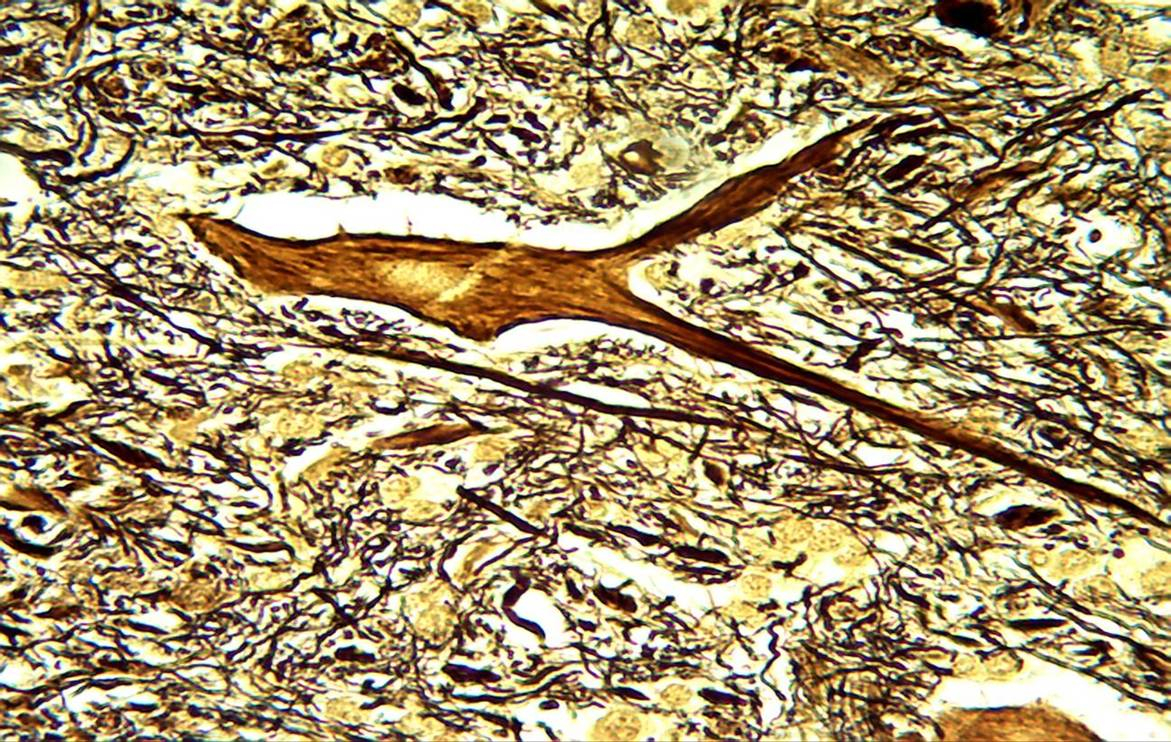

2013年7月24日~7月27日, 第六届组织学与胚胎学专业委员会暨全国医药院校组织学与胚胎学教研室主任会议、第十三届组织学与胚胎学青年学术研讨会、第十届组织学教学与科研技术经验交流会在广州医科大学召开。形态学实验室潘昭良主管技师带着精心制作的“脊髓神经组织切片银胺染色标本”荣获第二届“易创杯”组织学实验教学标本制作大赛二等奖。本次大赛未评出一等奖。